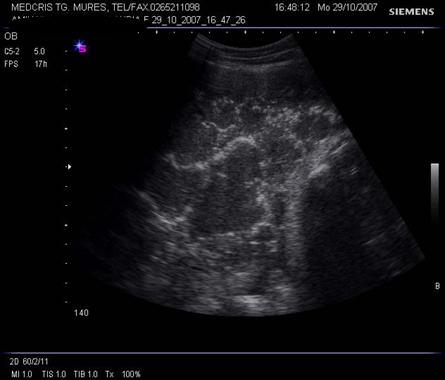

Fig. nr.211. Placenta grad. III la 41 saptamani gestationale, se remarca in structura placentara hiperecogenitati concentrice, in jurul unor zone relativ anecogene

Aparitia grd III inainte de 35 sapt, la maturatia placentei, a fost asociata cu greutate mica la nastere sau cu retard de crestere intrauterina.[9]

Calcificarile placentare (hiperecogene) sunt corelate cu hipertensiunea, retardul de crestere intrauterina si fumatul.

Lipsa maturarii placentare (grd 0 la 32 sapt) este o suspiciune de diabet gestational.